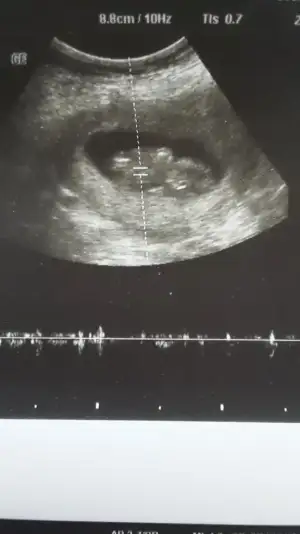

8+5günlük hafta var olursa ona bakın11 12 13 hafta usg olmalı burada 14 haftada nub oluşmuş oluyor sanki emin değilim erkek gibi gibi istediğim usg leride paylaşın![]()

10+5 burda Pazartesi kontrolüm var 12+1 olucaz inşallah atarım ozamanUsg net değil kaç hafta usg 12 13 de paylaşırsınız emin değilim sanki kız